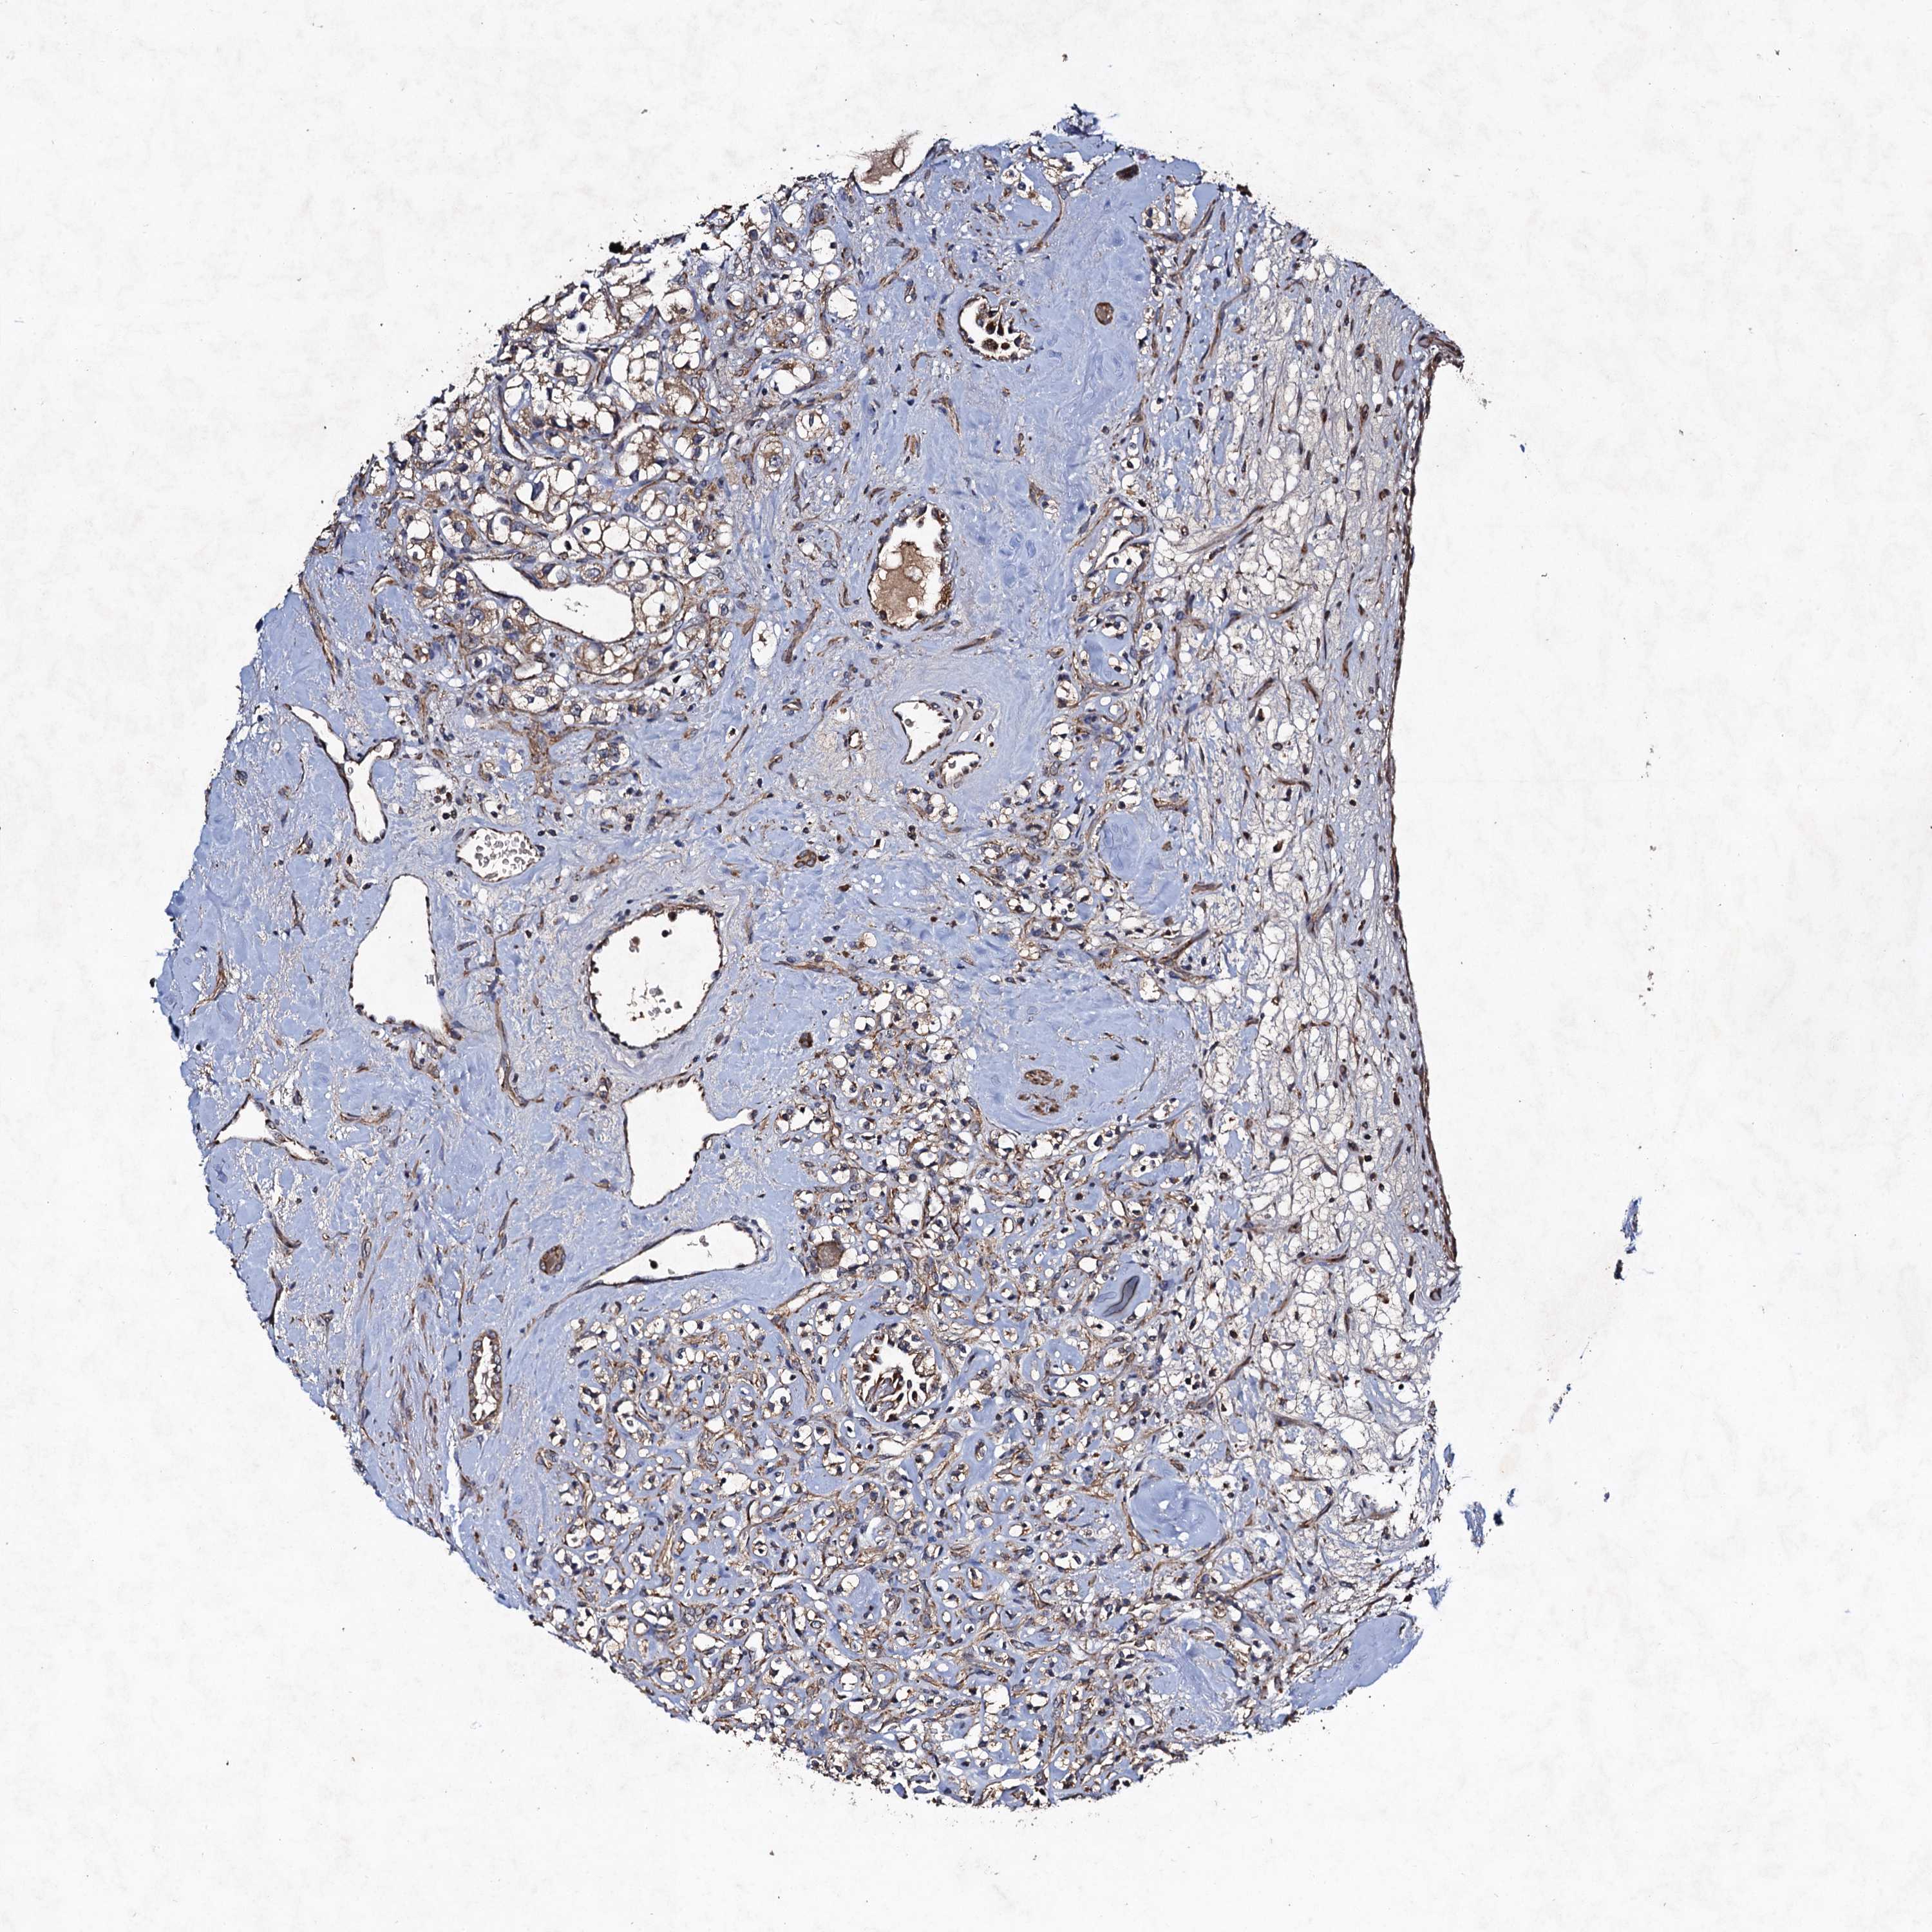

KIDNEY RENAL PAPILLARY CELL CARCINOMA (TCGA) - Interactive survival scatter ploti

The Survival Scatter plot shows the clinical status (i.e. dead or alive) for all individuals in the patient cohort, based on the same data that underlies the corresponding Kaplan-Meier plots. Patients that are alive at last time for follow-up are shown in blue and patients who have died during the study are shown in red.

The x-axis shows the expression levels (FPKM) of the investigated gene in the tumor tissue at the time of diagnosis. The y-axis shows the follow-up time after diagnosis (years). Both axes are complimented with kernel density curves demonstrating the data density over the axes. The top density plot shows the expression levels (FPKM) distribution among dead (red) and alive patients (blue). The right density plot shows the data density of the survived years of dead patients with high and low expression levels respectively, stratified using the cutoff indicated by the vertical dashed line through the Survival Scatter plot. This cutoff is automatically defined based on the FPKM cutoff that minimizes the p-score. The cutoff can be changed by dragging the vertical line or by entering a cutoff value in the square labeled "Current cut-off".

Under the Survival Scatter plot the p-score landscape (black curve; left axis) is shown together with dead median separation (red curve; right axis). Dead median separation is the difference in median mRNA expression between patients who have died with high and low expression, respectively. It is calculated as follows: median FPKM expression of dead patients with high expression - median FPKM expression of dead patients with low expression. This is intended to aid the user in visually exploring custom cutoffs and the associated p-scores and dead median separation.

Individual patient data is displayed and can be filtered by clicking on one or more of the category buttons on the top of the page. Categories describing expression level and patient information include: high, low, alive, dead, female, male and tumor stages. The scale of the x-axis can be toggled between linear and log-scale by clicking on the "x log" button. Mouse-over function shows TCGA ID, patient information and mRNA expression (FPKM) for each patient.

& Survival analysisi